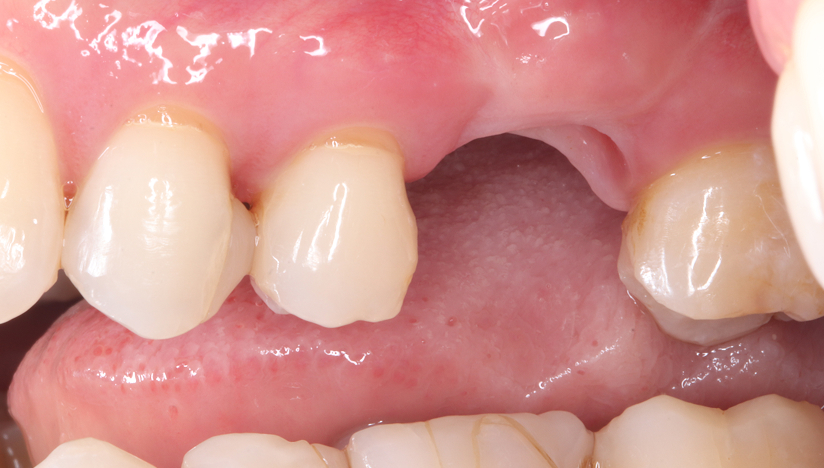

Before

After

主訴

奥歯で噛めない、歯茎が腫れてきた

治療内容

抜歯即時インプラント埋入1本、待時インプラント埋入2本、リッジプリザベーション(顎堤温存術)、GBR

治療期間

6〜8ヶ月

治療費用

1,947,000

治療の

リスク

オッセオインテグレーションが得られなかった場合、撤去、再度埋入の可能性